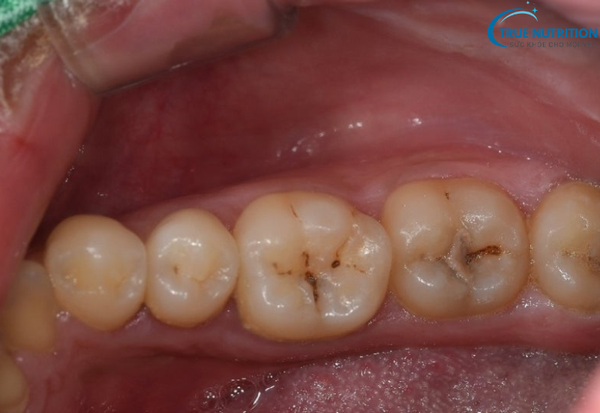

- Xuất hiện lỗ sâu: Lúc này, bạn có thể quan sát thấy một lỗ nhỏ hoặc vùng tối màu trên bề mặt răng. Lỗ sâu thường có màu nâu, xám hoặc đen, tùy thuộc vào mức độ nhiễm khuẩn và vị trí tổn thương.

- Đổi màu răng: Răng bị sâu nặng thường có màu nâu sẫm hoặc đen, mất đi độ bóng tự nhiên của men răng.

- Quan sát trực tiếp lỗ sâu, vết đổi màu trên răng.